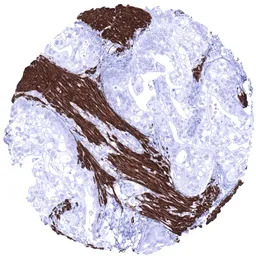

IHC-P analysis of human rhabdomyosarcoma tissue section using GTX04410 Desmin antibody [MSVA-651M] HistoMAX.

Soft tissue Strong desmin positivity of all tumor cells of a rhabdomyosarcoma.